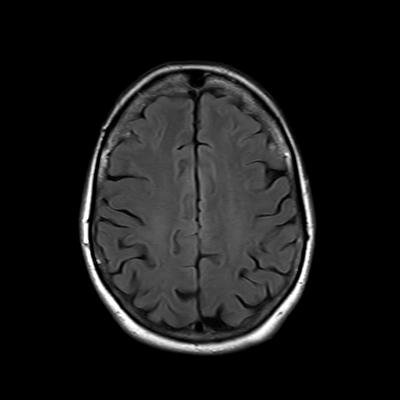

You also obtain an MRI of his brain once it's clinically safe to do so.

MRI brain (FLAIR)